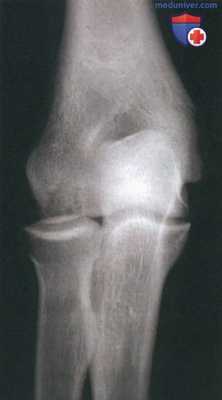

1. Стандартная рентгенография:

- Назначается рентгенография в передне-задней, боковой и плечелучевой (передне-задняя проекция при сгибании 45°) проекциях

- Сравнительная рентгенография противоположной конечности позволит выявить минимальные изменения

- На ранних стадиях заболевания изменений на рентгенограммах может не быть

- Локальная зона просветления в субхондральной кости локализуется в переднедистальной части головчатого возвышения. Этот участок окружен полоской субхондрального склероза и позднее ограничивается характерной полулунной зоной разрежения, называемой симптомом полумесяца (рис. 1)

- Часто в полости сустава можно увидеть свободные тела

- Более старые очаги могут ограничиваться хорошо выраженной зоной склероза

- Может наблюдаться изменение формы и увеличение размеров головки лучевой кости